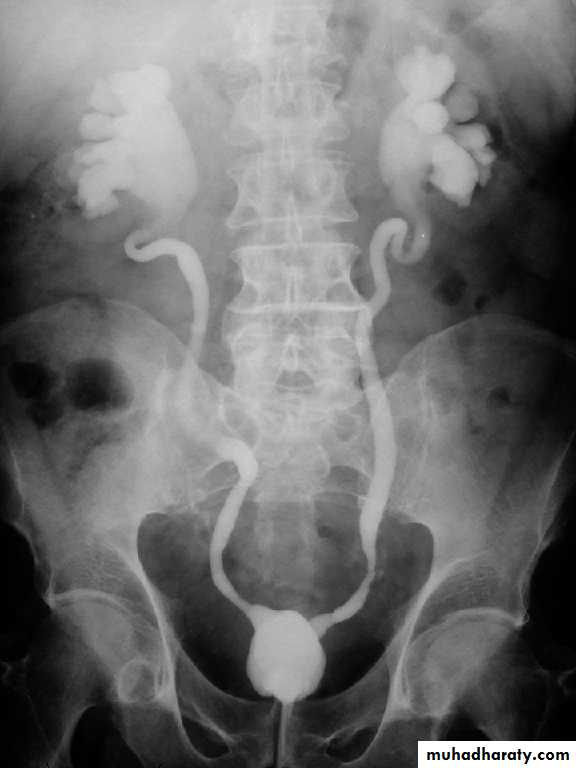

Intravenous Urography (IVU)